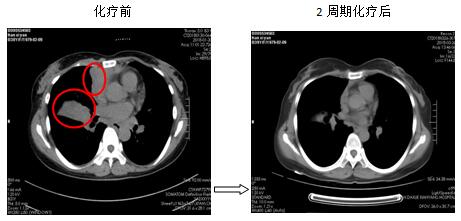

針對(duì)每一例化療患者,參照最新NCCN指南(為腫瘤診療的國(guó)際權(quán)威指南),為患者制定規(guī)范、有效的個(gè)體化化療方案。2周期化療后評(píng)價(jià)療效:其中1例肺癌肉瘤術(shù)后的胰腺占位的患者,2次化療后胰腺占位基本消失,另有1例非小細(xì)胞肺癌伴肺、心包、肝多發(fā)轉(zhuǎn)移患者,2次化療后肺部、肝內(nèi)病灶顯著縮小,其余化療患者還未到療效評(píng)價(jià)時(shí)機(jī)(指南推薦每2周期評(píng)價(jià)化療療效)。

圖2. 肺癌伴多發(fā)轉(zhuǎn)移患者,化療后肺、心包、肝臟病灶明顯縮小